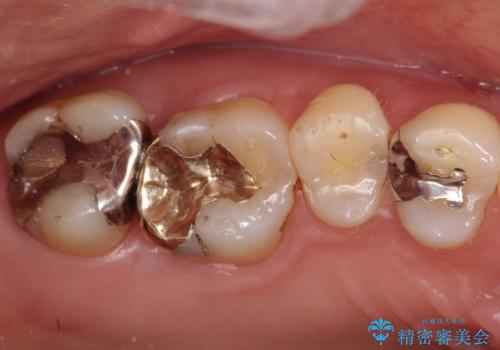

銀歯が外れてしまった ゴールドインレーによる補綴治療

- 銀歯が外れて、中が虫歯になっているところがありました。

虫歯を取り除き、ゴールドインレーを装着する治療計画としました。